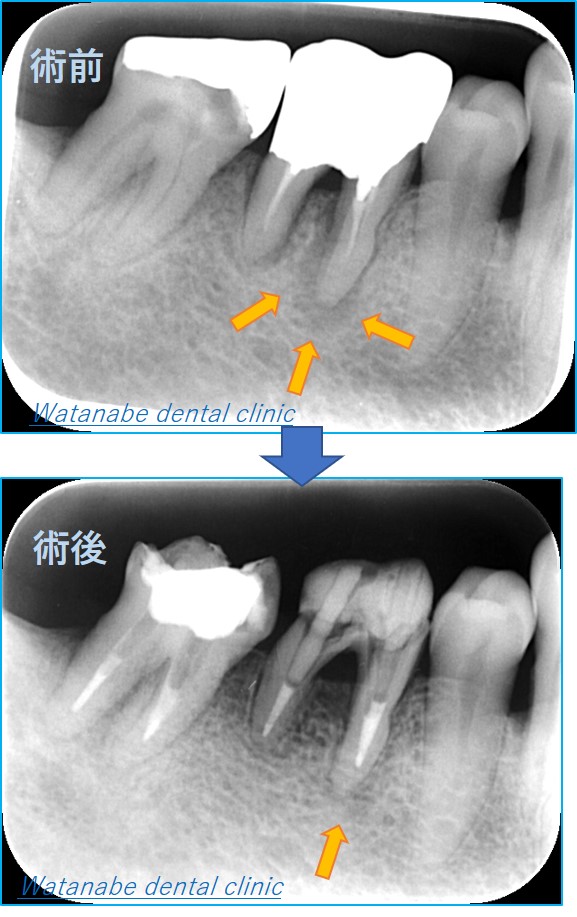

写真は根管治療の術前(上)および術後(下)の写真です。

術前写真(上)のオレンジの部分に黒い影が見えます。これは、以前に「歯髄」を取られて感染しています。つまり、根管内で細菌が増殖しているため根の先に炎症が波及して骨が溶けている状態なのです。治療法としては、「根管治療」を行う必要があります。一度細菌感染した根管内の消毒を行います。その結果、下写真では骨再生が観察され完治しています。